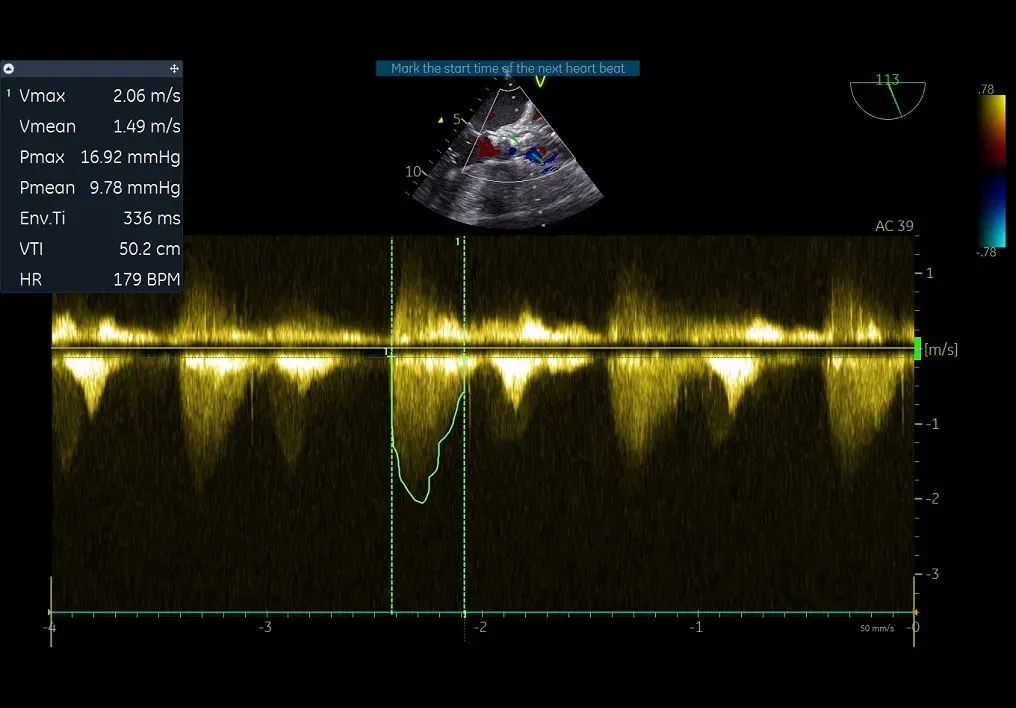

术前超声评估:

主动脉瓣狭窄(重度),收缩期主动脉瓣上流速增快,最大流速约4.5m/s,最大压差约82mmHg,平均流速约3.3m/s,平均压差约49mmHg。左室肥厚,左室舒张功能减低。D-Dimer5.22mg/1FEU,NT-proBNP780.3pg/ml,hsTNI最高270pg/ml,CK-MB最高4.9ng/ml,肌酐56μmol/L,血钾3.7mmol/L。双下肢大动脉超声显示双侧股动脉多发斑块。双侧锁骨下动脉超声未见明显异常。双侧颈动脉超声显示颈动脉内中膜增厚、斑块形成。双下肢深静脉超声显示双下肢深静脉未见血栓。主动脉+腹主动脉+髂动脉CTA:主动脉、髂动脉粥样硬化,主动脉瓣钙化。冠脉造影显示RCA中重度狭窄,于RCA植入支架2枚。